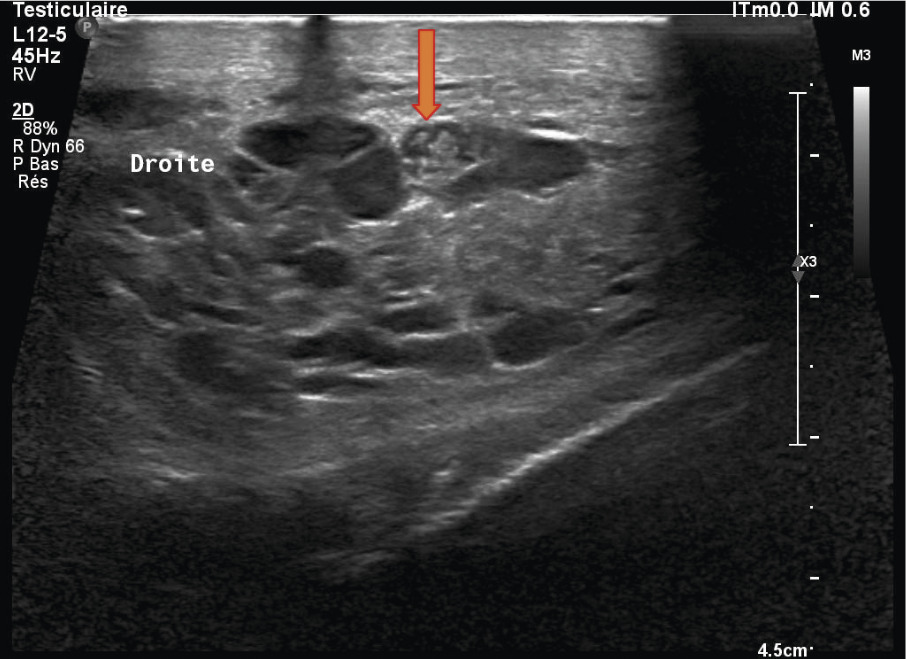

Une échographie testiculaire est réalisée. Elle ne décèle aucune anomalie épididymaire ni testiculaire et constate l’absence d’hydrocèle, mais la présence d’une varicocèle droite abondante dont certaines cavités ont un contenu hétérogène, mobile et échogène (filarial dance) évoque une parasitose (figure).

Le diagnostic de filariose lymphatique est confirmé par la mise en évidence des microfilaires sanguicoles nocturnes. L’échographie des voies séminales visualise assez souvent des images de filaments animés de mouvements ondulants, décrits sous le nom de « filarial dance »4, et longtemps considérés comme pathognomoniques. Néanmoins, ce phénomène a été constaté chez des sujets non filariens (biopsies montrant des agglomérats de spermatozoïdes5,6).